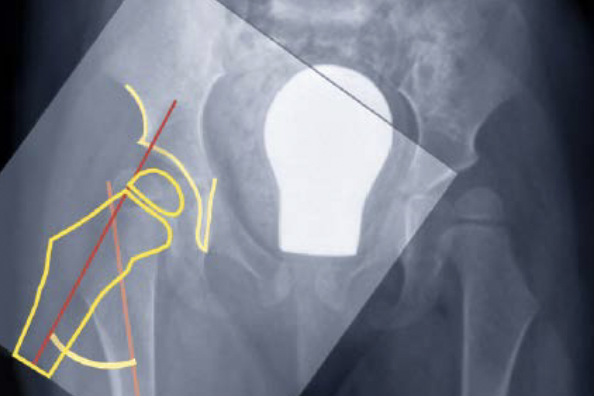

Reshaping osteotomy

Indication

Lateral deficiency

Abnormal acetabular shape

Concept

Dega / Pemberton

- incomplete iliac supra-acetabular osteotomies

- anterior and middle thirds of ilium, stop short of sciatic notch

- bend through tri-radiate cartilage

Technique

- curved osteotomes

- 15 mm above and parallel to superior dome of acetabulum

- leave posterior column intact

- bone graft +/- K wires